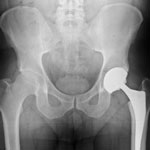

A ceramic-on-ceramic device, the Stryker Trident hip implant was designed to produce less wear and tear than metal and plastic materials. Laboratory testing had shown the ceramic materials to demonstrate less wearing because of the hardness of the material.

In January 2008, Stryker implemented a Stryker hip recall withdrawing several Trident ceramic hip components from the market. These components were blamed for complications like inflammation and pain, squeaky joints, bone fractures, and failure of the implant.